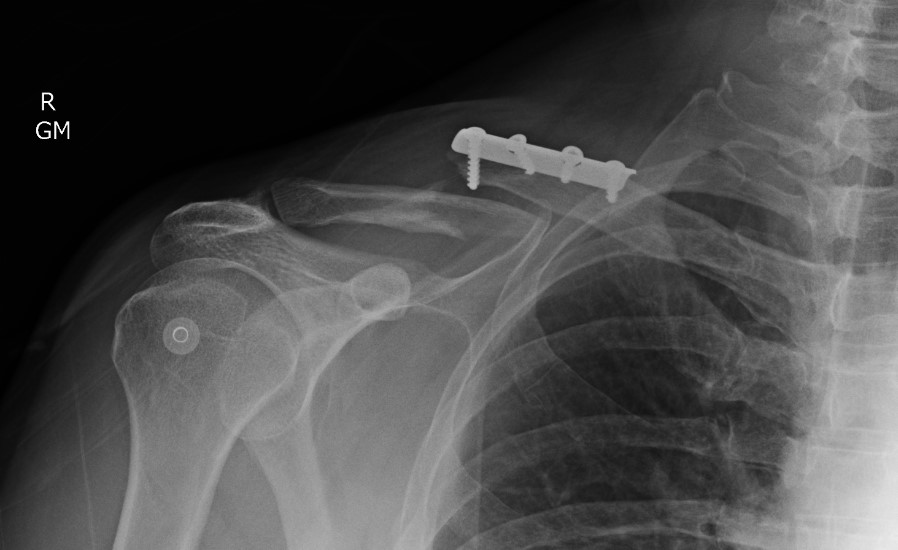

Compound clavicle fracture

Shorted / displaced midshaft clavicle fractures

Z shaped midshaft clavicle fracture

Plate fixation of shorted displaced midshaft clavicle fractures reduces nonunion rates

Operative Management

Plate fixation

Superior versus anteroinferior plates